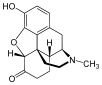

In the 19th century, two major scientific advances were made that had far-reaching effects. Around 1804, German pharmacist Friedrich Sertürner isolated morphine from opium. He described its crystallization, structure, and pharmacological properties in a well-received paper in 1817.[211][213][208][214] Morphine was the first alkaloid to be isolated from any medicinal plant, the beginning of modern scientific drug discovery.[211][215]

Several semi-synthetic opioids were developed in Germany in the 1910s. The first, oxymorphone, was synthesized from thebaine, an opioid alkaloid in opium poppies, in 1914.[228] Next, Martin Freund and Edmund Speyer developed oxycodone, also from thebaine, at the University of Frankfurt in 1916.[229] In 1920, hydrocodone was prepared by Carl Mannich and Helene Löwenheim, deriving it from codeine. In 1924, hydromorphone was synthesized by adding hydrogen to morphine. Etorphine was synthesized in 1960, from the oripavine in opium poppy straw. Buprenorphine was discovered in 1972.[228]

- Natural opiates: alkaloids contained in the resin of the opium poppy, primarily morphine, codeine, and thebaine, but not papaverine and noscapine which have a different mechanism of action

Opium alkaloids and derivatives

Opium alkaloids

Phenanthrenes naturally occurring in (opium):